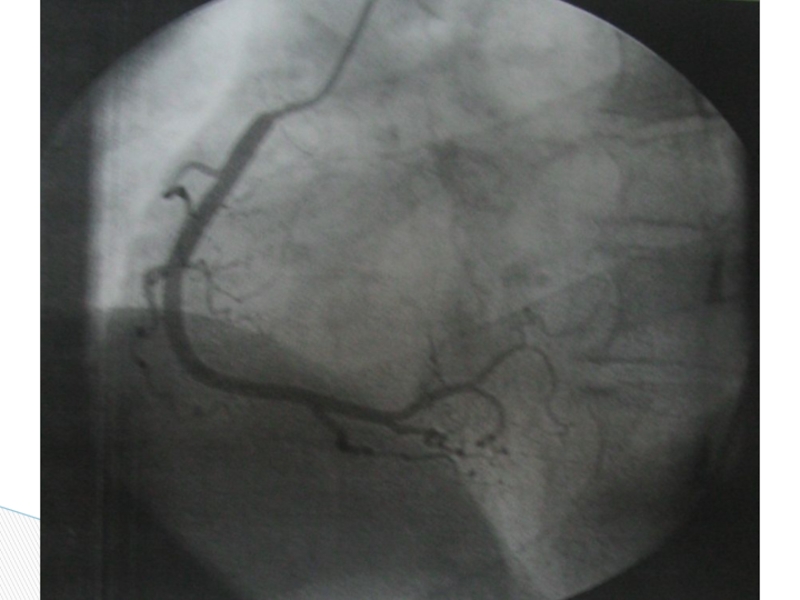

Слайд 39 Коронароангиография позволяет определить степень поражения коронарных артерий и провести ЧКВ:

Коронароангиография позволяет определить степень поражения коронарных артерий и провести ЧКВ:	стентирование	баллонирование